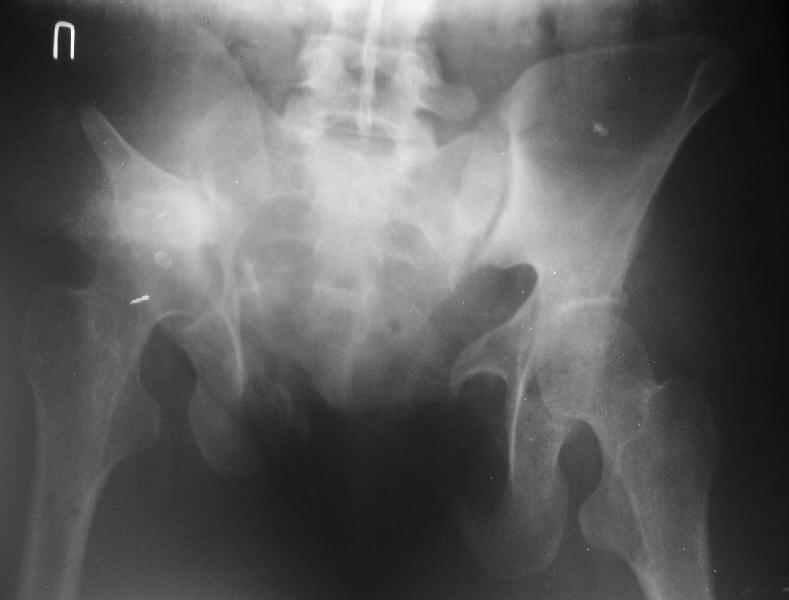

Госпитализирована больная 27 лет. Травма 1.5 года назад, сбита авто. При поступлении в местной больнице наложен фиксационный аппарат-«передняя рама». Через месяц аппарат снят из-за нагноения, разрешена ходьба с костылями. В послеоперационном периоде отмечалось нагноение забрюшинной гематомы. При обрашении к нам 3 мес назад в области промежности имелся свищ, по месту жительства выполнено иссечение свища, был гнойный затек на бедре, откуда получено до литра гноя, больная ходила с костылями.Свищ зажил 1,5 мес назад При поступлении сейчас укорочение до 5 см, ходит без дополнительной опоры, имеется выраженная хромота.Какой, по вашему, может быть оптимальная тактика оперативного лечения? Ограничиться низведением вертлужной впадины (каким доступом?), выполнить полную реконструкцию передних и задних отделов, одномоментно или поэтапно? Заранее благодарен.

По просьбам коллег отправляем снимки таза: прямая, inlet, outlet, 2 дополнительные компьютерные томограммы.